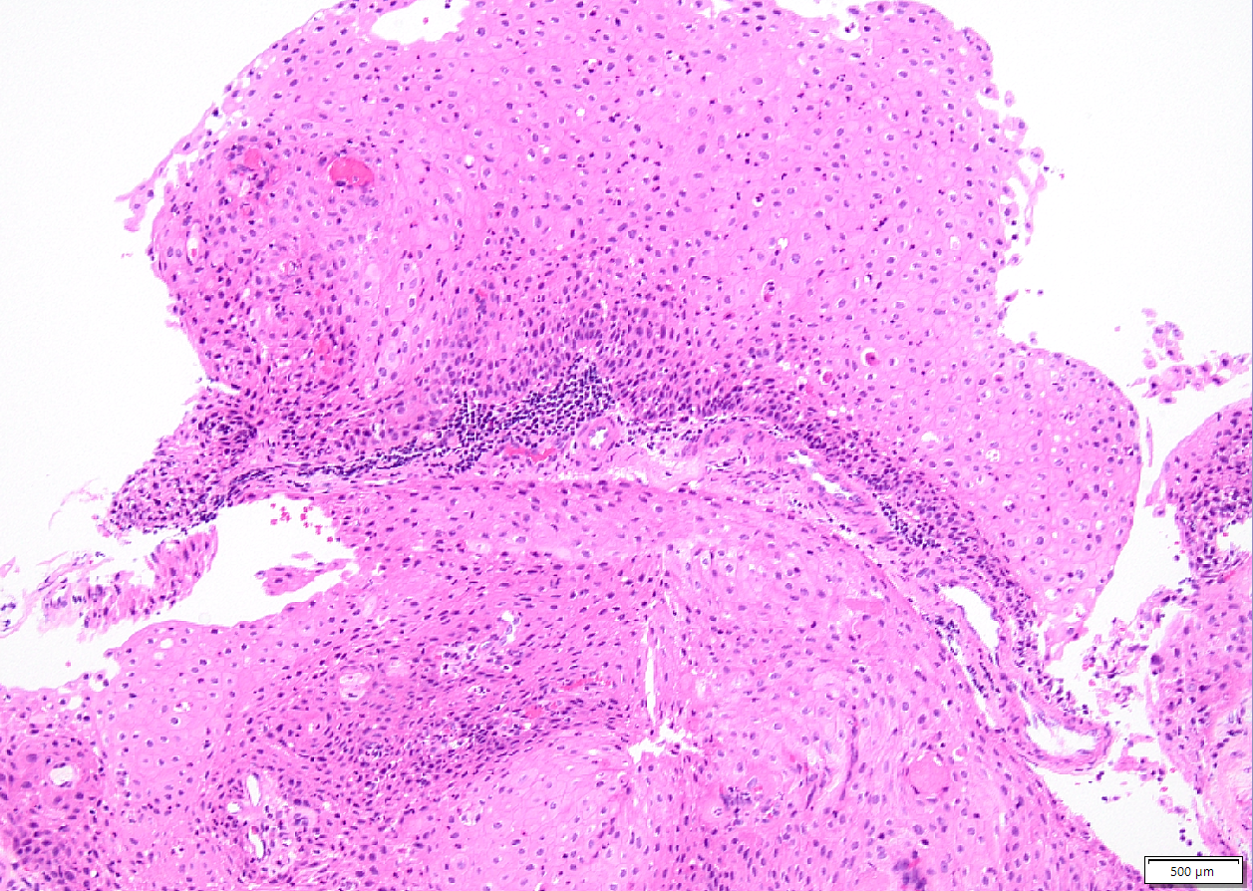

Case History:

A 45-year old man with a history of PTC, tall cell variant (PT3b N1a M0), s/p total thyroidectomy, central neck lymph node excision and radioactive iodine therapy, presents with new neck mass. Figures a & b show FNA of the mass.